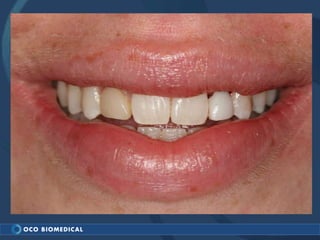

A 3.0mm dental implant was placed to replace congenitally missing maxillary lateral incisors. Dr. Tim Kosinski used a 1.8mm pilot bur and tissue punch to prepare the osteotomy site, then placed the implant by hand and seated it with a torque wrench. After ensuring the implant trajectory was within the restorative envelope, an acrylic coping was placed for temporary fabrication. At the 1 week post-op appointment, excellent soft tissue response and papilla formation were observed, and a final impression was taken to send to the lab for crown fabrication.